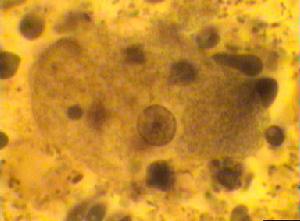

溶組織內阿米巴滋養體形態

溶組織內阿米巴包囊1.滋養體溶組織內阿米巴的滋養體大小在10~60μm之間,當其從有症狀患者組織中分離時,常含有攝入的紅細胞,有時也可見白細胞和細菌。滋養體藉助單一定向的偽足而運動,有透明的外質和富含顆粒的內質,具一個球形的泡狀核,直徑4~7μm。纖薄的核膜邊緣有單層均勻分布、大小一致的核周染色質粒(chromatin granules)。但在培養基中的滋養體往往有2個以上的核,核仁小,大小為0.5μm,常居中,周圍圍以纖細無色的絲狀結構。